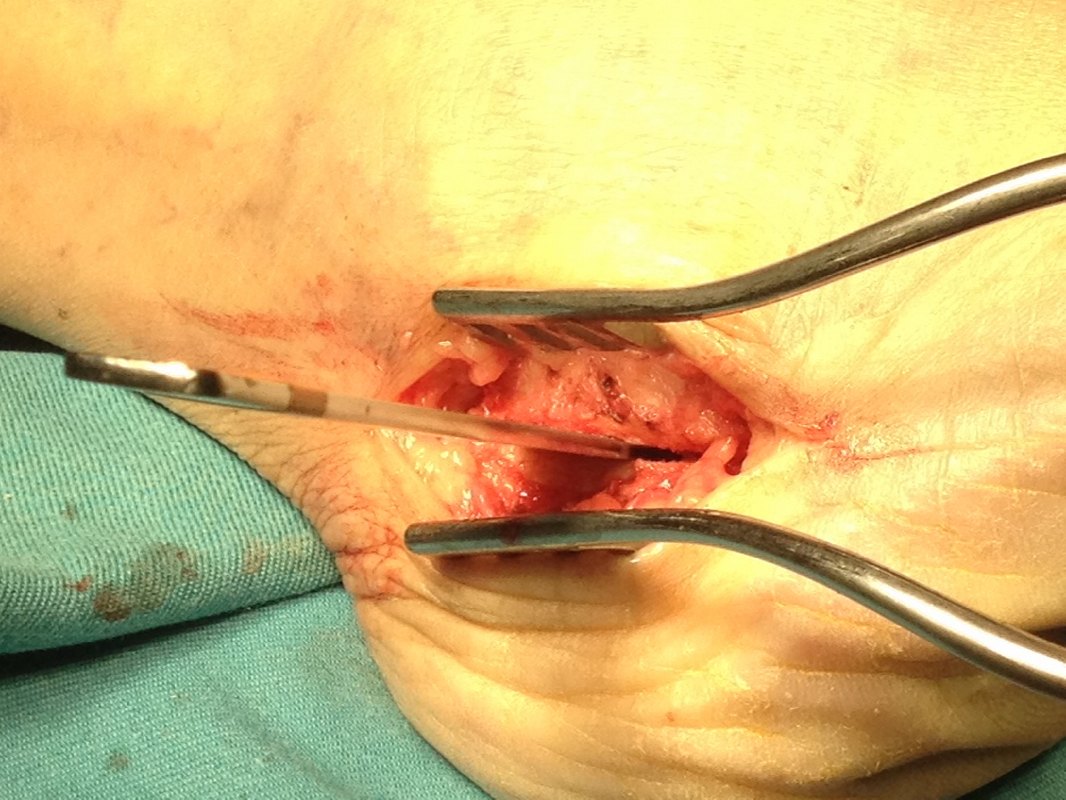

Note the tenosynovitis of the posterior tibial tendon sheath. This is a source of pain and should be excised.

The FDL tendon is harvested and it will be used to augment the functions of the posterior tibial tendon to lift up the medial arch of the foot.